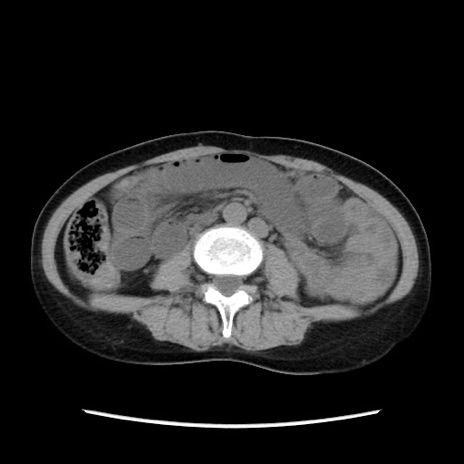

症例32(横断像)

【症例】40歳代 女性

【主訴】上腹部痛、嘔気・嘔吐

【現病歴】約9時間前頃から急に上腹部痛、嘔気、嘔吐が出現。改善しないため救急要請。

【既往歴】子宮頚癌(広汎子宮全摘術、放射線療法)、腸閉塞

【身体所見】腹部:平坦、軟、腸雑音亢進、上腹部を中心に腹部全体に圧痛あり。

【データ】WBC 8400、CRP 0.03